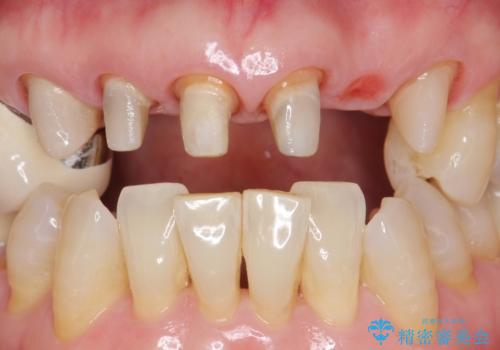

上の前歯6本はメタルボンドクラウン(内側が金属の被せ物)で補綴されており、顕著な歯肉退縮を認めました。

被せ物を除去したところ根管治療後の処置が不十分であったため、ファイバーコア(金属を用いない強くてしなやか材質の土台)を植立したのち、ジルコニアセラミッククラウンによる治療を行いました。

また、古い被せ物はブリッジではない右上321も連結されていましたが、1本1本の歯の動揺がなく連結する必要がないと判断し単冠による補綴を行いました。

単冠の部位は天然歯のようにフロスを通すことができるため、セルフメンテナンスもしやすくなったと患者様に喜んで頂けました。